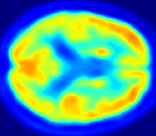

Looking at sample synthetic PET images in Fig. 3, it can be seen that all of the models are able to make reasonable predictions. The outputs of the U-PET and U-PET (no att.) look very similar and are smoothed compared to the input. The pix2pix predicts more details, which seem to be important for the discriminator. However, even though this model has finer predictions, the intensity values are worse compared to the U-PET and U-PET (no att.) as seen in Fig. 2; an example is given in Fig. 3 in the second row.

From a clinical perspective, the synthetic generated PET show a smoother version of the real PET images but keep the same pattern of FDG uptake, especially, hypometabolism in the respective brain areas. This backs up our hypothesis, that MRI contains information that correlates with the functional information of PET images. Moreover, the synthetic PET could be used as complementary visualization for physicians beyond the task of classification.

| MRI | PET | Synthetic PET | AttMap skip | AttMap |

In Fig. 4, the attention maps of the U-PET are shown for multiple examples. On the one hand, the attention map of the skip connection (AttMap skip) highlights details of the brain structure, which is in agreement with the assumption that the network has to transform the specific structures of the MRI scan into the PET modality. On the other hand, the attention gates used for the classification task rather focus on more specific regions. One can observe a trend that the attention maps used for classification tend to highlight regions which have a low uptake in the PET. Since areas with a lower uptake in the PET correspond to areas with lower functional activity (hypometabolism), this focus area of the network seems reasonable with respect to the classification task.